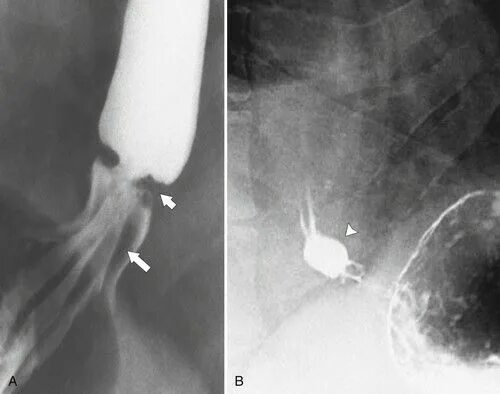

Кольцо шацкого в пищеводе что это